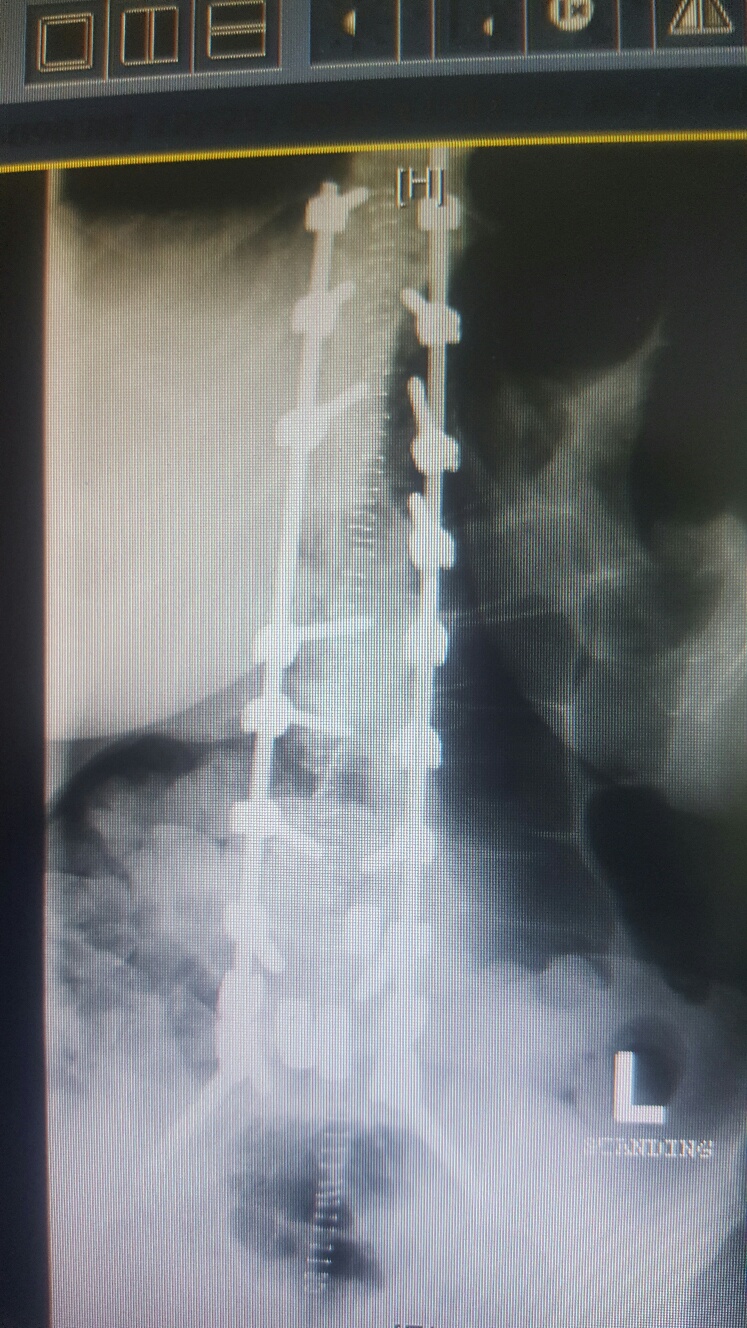

after the fix:

20161221_145625_resized_3.jpg

(if you look closely you can see the staples!)

20161221_145639_resized_2.jpg

i am pretty darned close to 0 degrees on the scoliosis!!!! and my spine isn't twisted anymore either! it feels totally different to walk, sit, stand, basically to do anything, but that's okay! the square things in the after xrays are cages to replace the discs that were removed.

so they removed the backs off the vertebrae at L2 L3 L4 and L5 it looks like from the xrays. took out all the facet joints (the bars are where they would be)....so that freed up all the pinched nerve roots and took the pressure off my spinal cord.